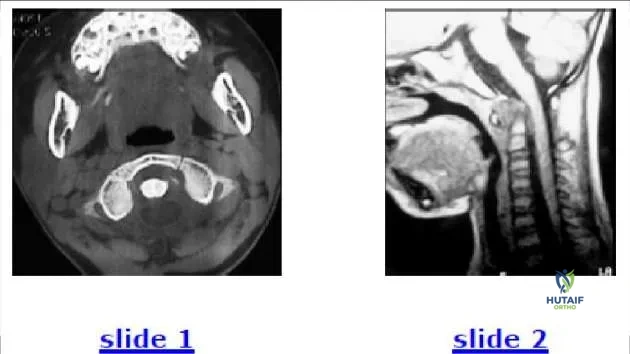

Question 19:

A 6-year-old child is involved in a motor vehicle accident. What injury is demonstrated by the computed tomography (C T) (Slide

This patient has an avulsion injury of the transverse ligament of the atlas. The bony avulsion is visible from its attachment to the left lateral mass and allows the atlas to move forward in relation to the axis. Hematoma and occiptocervical flexion is visible on the MRI. If it were an

odontoid injury, the odontoid would still have a normal relationship to the ring of C 1 on the C T. Treatment involves reduction and fusion of C 1-C 2.